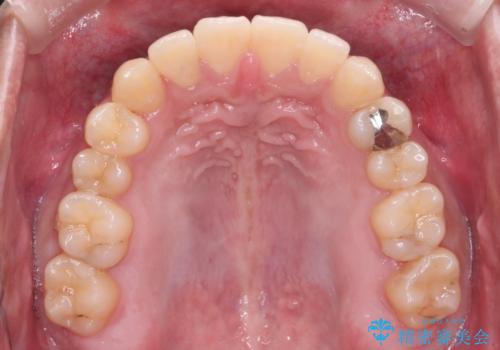

【クリア装置】八重歯とがたつきを綺麗に

- 上の八重歯と下の歯のがたつきを主訴に来院されました。

矯正検査の結果、抜歯はせずに

臼歯を遠心移動させ、歯列をワイヤーで整えることでスペースを確保し、IPR(歯と歯の間を削る処置)を加えて歯並びを綺麗にする治療計画を立てました。

歯の移動にオープンコイルとMI(歯肉に埋入するネジ)を用いました。

非抜歯矯正だったこともあり、1年半以内という短い期間で矯正を終了することができました。

気にされていた八重歯とがたつきが綺麗に改善されました。